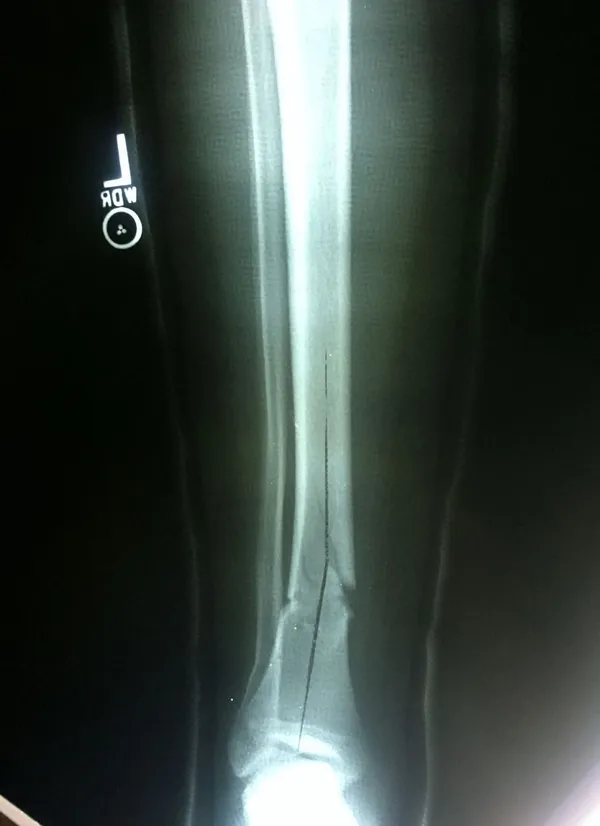

Pictured below is an x-ray of a more severe diaphyseal fracture of the tibia from higher velocity impact. This can heal without surgery but must be carefully monitored with above the knee casting to eliminate tibial torsional force from the knee or ankle.